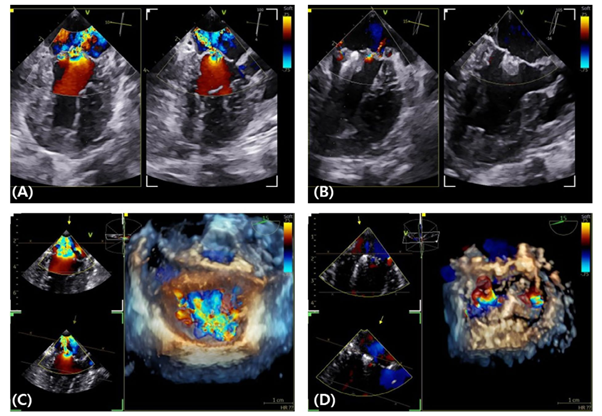

이번에 발표된 연구에는 KAMC에서 TEER 수술을 받은 8살에서 14살의 체중 2.05kg부터 7.8kg까지의 이첨판 페쇄부전증(MMVD) B2, C, D단계의 개들이 포함됐다. 논문에는 TEER 수술을 받은 개에서 수술 전과 3개월에 걸쳐 나타나는 이첨판 역류량(Regurgitatn volume), 심장 크기, 처방 약물 등의 변화, 합병증을 자세히 설명하고 있다.

연구 결과에 따르면, 실제로 TEER 수술 이후 3개월 차에 이첨판 역류량이 3.96ml/kg에서 1.25ml/kg까지 감소하는 모습을 보였으며, 좌심방 대동맥 비율(LA/AO), 체표면적 보정 좌심실 이완기 내경(LVIDDn) 등 좌심의 용적 과부하를 의미하는 지표들의 유의미한 개선이 확인됐다.

이정민 수의사는 “이첨판 폐쇄부전증의 관리에서 환자에게 약물적 관리가 더 적절한지, 또는 수술적 치료를 고려해야 하는지를 정확히 평가하는 것이 중요하다”고 강조하면서 “이러한 요소들을 판단하기 위해 경식도 초음파를 통한 3D 심장 재구성이 큰 도움이 된다”고 밝혔다.

경식도 초음파를 활용해 정밀한 심장 구조 및 역류량을 평가할 경우 이첨판 폐쇄부전증 환자에게 보다 명확하고 적극적인 맞춤형 처방이 가능하다. 또한 TEER 수술에 있어 내과, 외과, 영상의학과, 마취과, 중환자응급의학과 간의 긴밀한 협진 역시 치료 결과에 중대한 영향을 미친다.